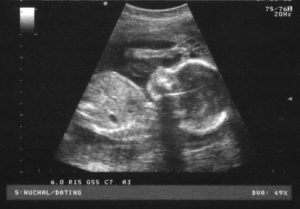

Для диагностики гипертонуса используется ультразвуковое исследование, при проведении которого может быть выявлен гипертонус задней стенки матки, а также передней. Однако, этот признак не всегда может говорить об угрозе прерывание беременности. Матка может прийти в тонус в ответ на прохождение ультразвуковой волны через ее стенку.

Тонус матки определяется по результатам ультразвукового исследования. УЗИ показывает изменение формы плодного яйца. Причины преждевременного сокращения бывают разные. Это и разного рода заболевания, обычно связанные с эндокринной системой, а также болезнями матки: эндометриоз, миома, цервикальная недостаточность. Данный недуг может быть также генетически обусловлен.

При необходимости назначается ультразвуковая диагностика, позволяющая дать правильную оценку состояния шеечного канала и толщины мышечного слоя органа. Маточное напряжение также может обнаружиться посредством тонометрии, при которой на животе фиксируются специальные датчики.

Хотя чаще все же используется пальпация и УЗИ.

Важно! Часто во время проведения УЗИ врачи диагностируют гипертонус. Но это не говорит об угрозе преждевременных родов – это всего лишь реакция мышц на проведение датчиком по животу.